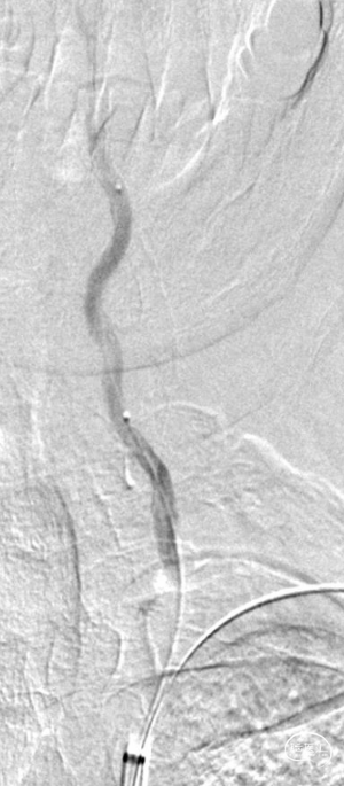

造影:

患者左侧椎动脉稍优势,右侧椎动脉开口重度狭窄、次全闭塞,左椎开口重度狭窄。

微导丝、球囊到位:

置入0.018inch*300cm微导丝至左锁骨下远端,以0.014inch*200cm微导丝携带0.017inch微导管进入左侧椎动脉V2段,微量造影确认位于血管真腔。通过0.014inch*300cm微导丝交换技术,将2.0mm*20mm球囊扩张导管置入左侧椎动脉V1狭窄段。

球囊预扩:

2.0mm*20mm球囊扩张导管置入左侧椎动脉V1狭窄段,造影确认后予以10 atm预扩张;球囊扩张后患者狭窄较前改善。